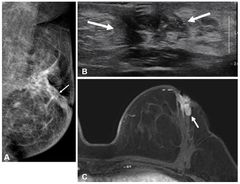

수술 전 MRI가 50세 이하 유방암 환자의 재발 예방에 효과적이라는 사실을 서울대병원 연구팀이 규명했다. 특히 예후가 나쁘고, 재발률이 높은 ‘호르몬 수용체 음성 유방암’은 재발

국내 연구진이 수술 전 MRI(자기공명영상)가 50세 이하 유방암 환자의 재발 예방에 효과적이라는 사실을 규명했다. 특히 예후가 나쁘고 재발률이 높은 '호르몬 수용체 음성 유방암'

[헬스코리아뉴스 / 박원진] 수술 전 MRI가 50세 이하 유방암 환자의 재발 예방에 효과적이라는 연구 결과가 나왔다. 특히 예후가 나쁘고, 재발률이 높은 ‘호르몬 수용체 음성 유